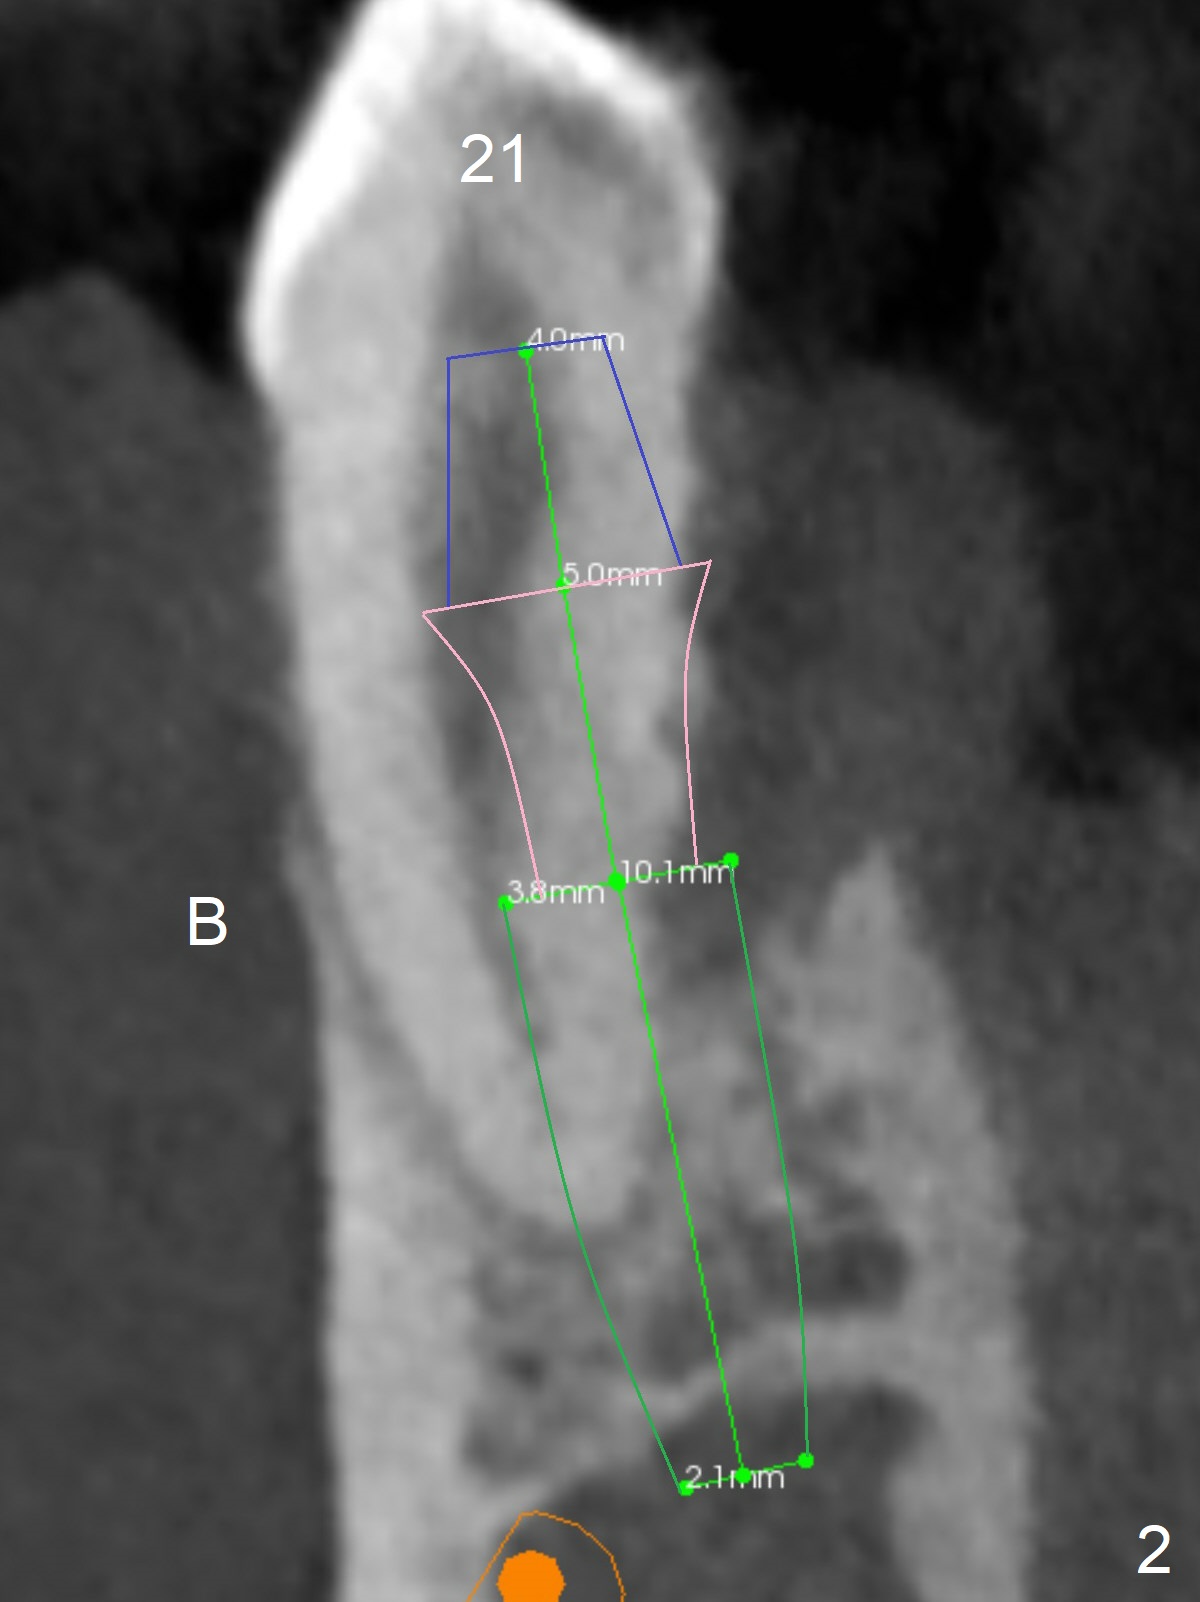

A 36-year-old man develops periodontal abscess at #19 and 20 after scaling & root planing. Since the site of #20 is close to the Mental Nerve, 3.8 mm tap or dummy implant will be used to form osteotomy instead of drills (Fig.1,3). While an implant will be placed in the middle of the socket #20, an implant will be placed as buccal as possible at #19 (Fig.4). If primary stability at #20 is poor, extract the tooth #21 and place a 3.8x10 mm lingually (Fig.2). PRF membrane will be placed prior to bone graft after implant placement (Fig.3 yellow).